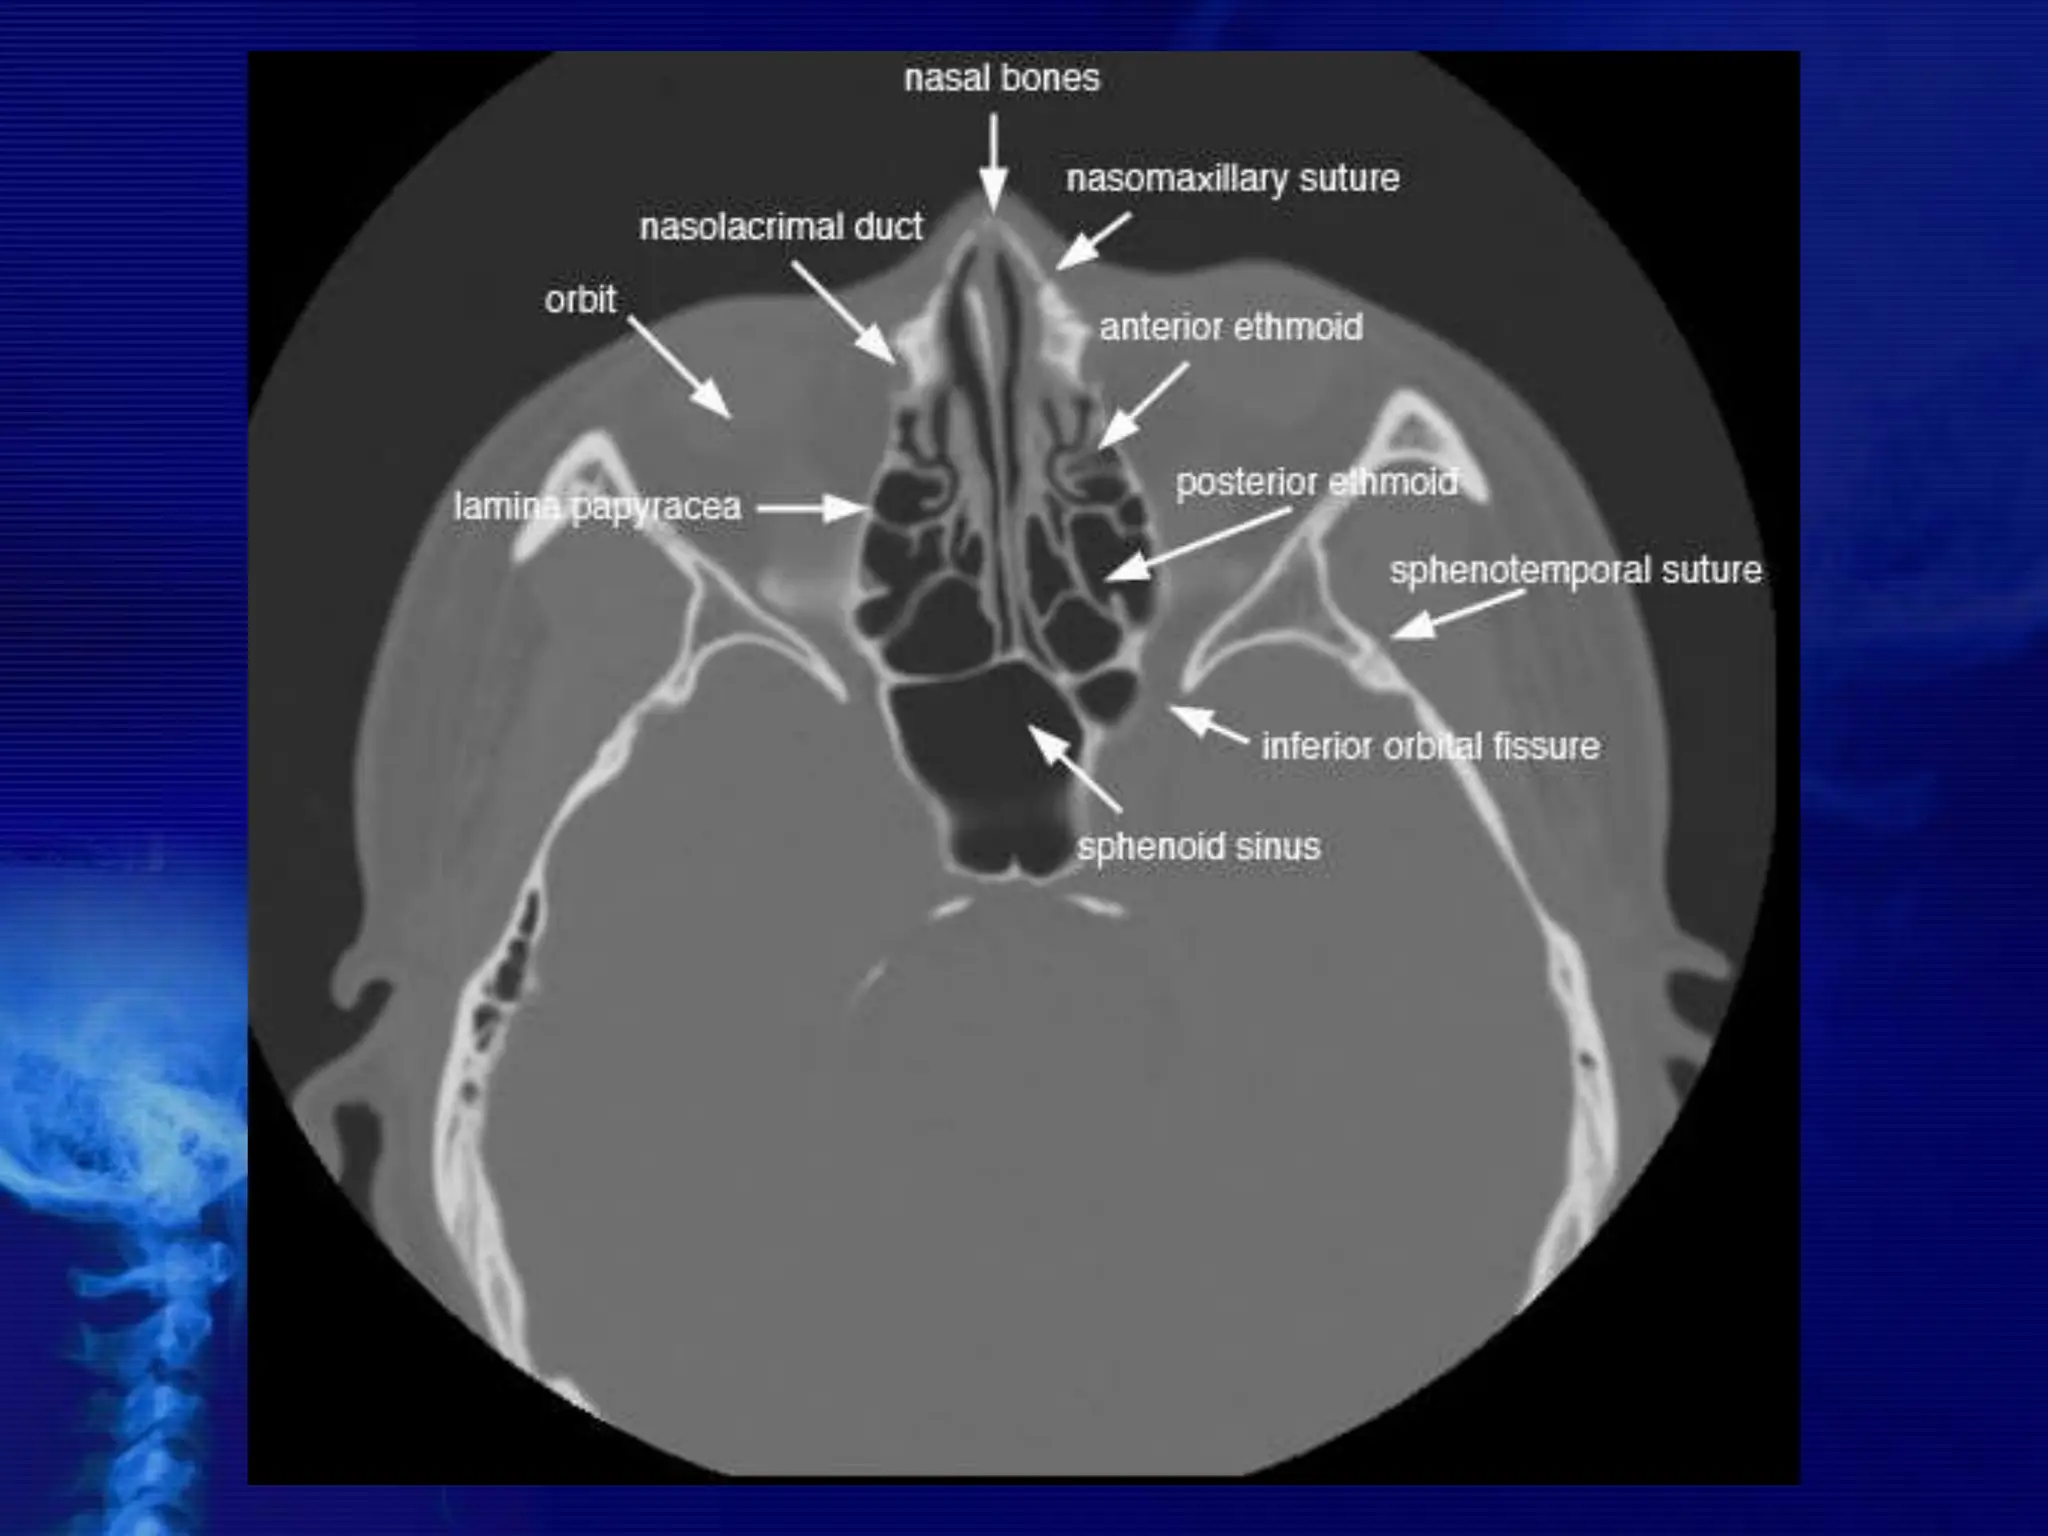

CROSS SECTIONAL ANATOMY –

AXIALS